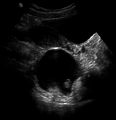

A complex cyst due to a dermoid as seen on ultrasound